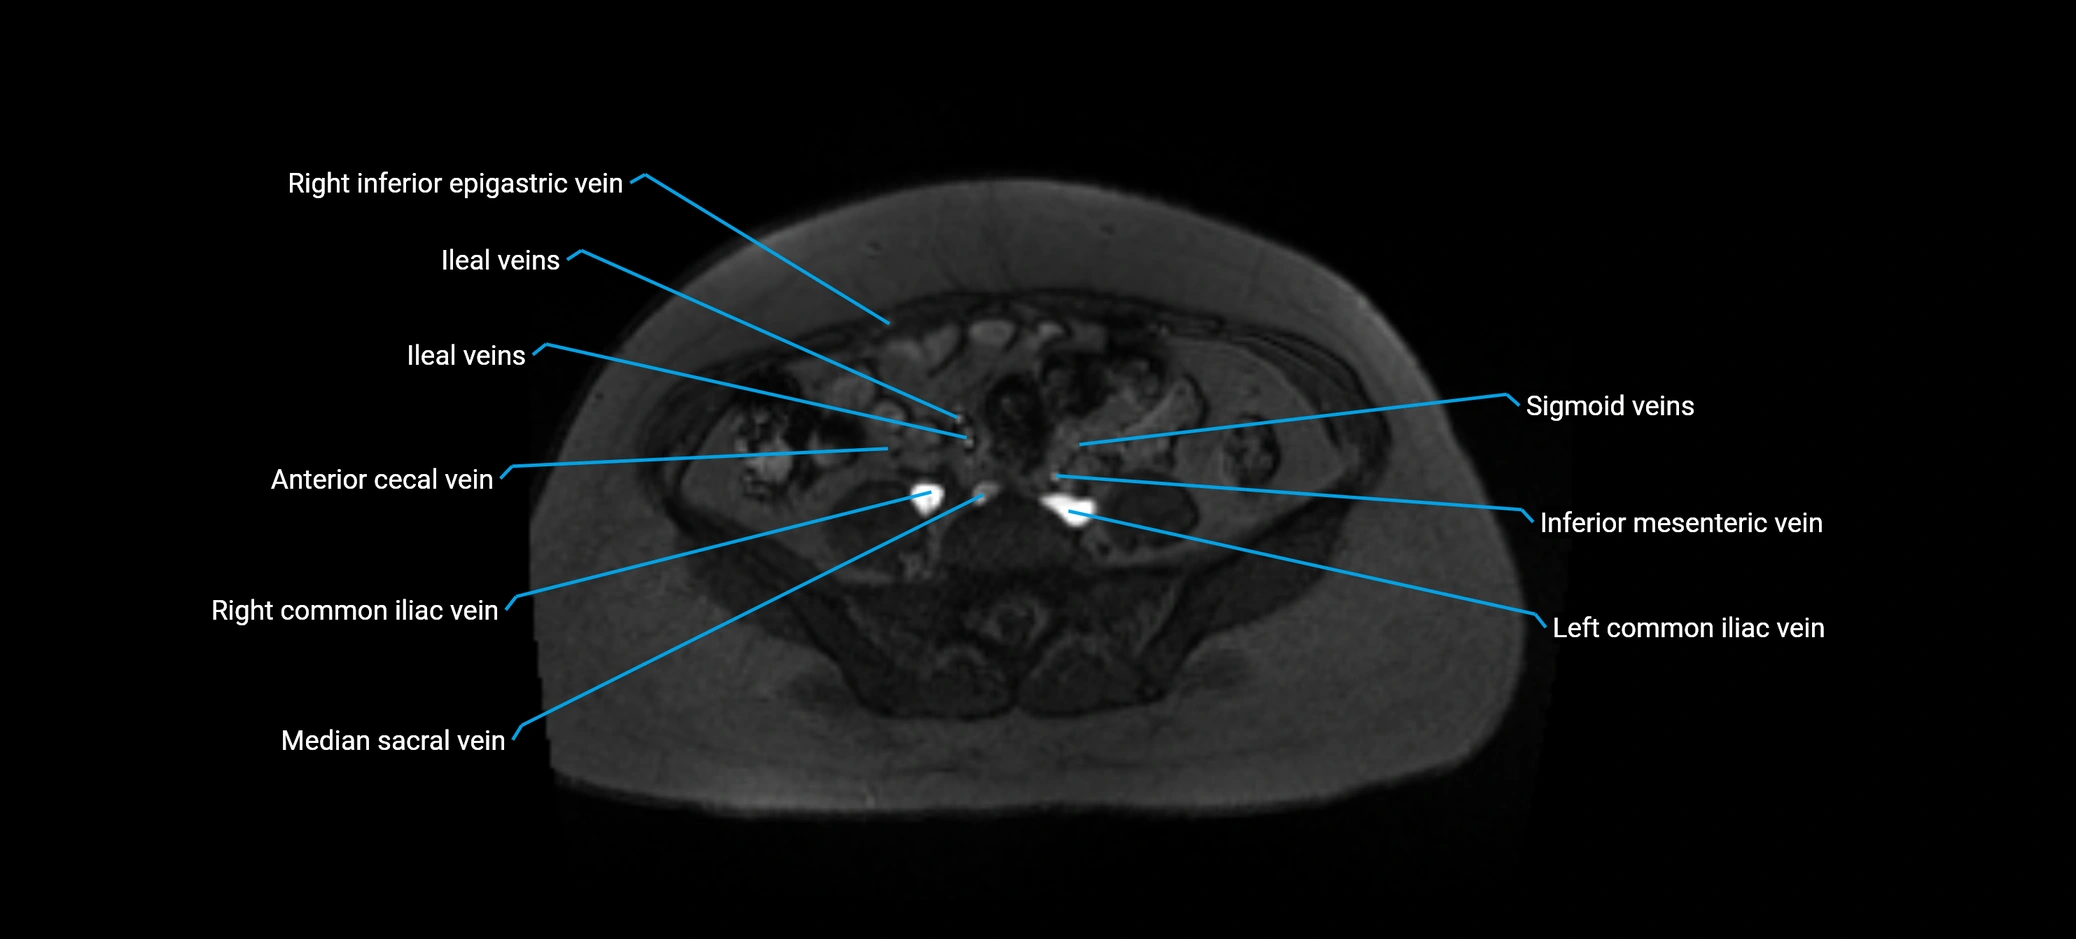

MRI image

image